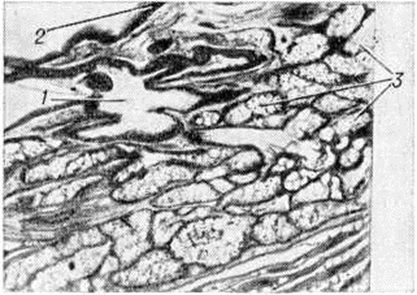

Дермоид обязательно содержит ткани, не характерные для данной области и не образующиеся в процессе метаплазии местных тканевых элементов. Дермоид обычно имеет округлую, не всегда правильную форму, гладкую или чуть бугристую поверхность. Величина его от долей сантиметра до крупных размеров. Консистенция плотноэластическая или тестоватая, неоднородная на различных участках. Дермоид бывает однокамерным и многокамерным, содержимое его — сало или желеобразные массы различной густоты, сероватого или буроватого цвета, с клубками волос. Комки сальной массы состоят из слущённых клеток плоского эпителия, кристаллов холестерина и аморфного жира; стенка кисты состоит из плотной соединительной ткани с участками обызвествления, иногда содержит хрящевую или костную ткань. Внутренняя поверхность часто имеет вид кожи и выстлана многослойным плоским эпителием (рисунок 1). Глубже расположены сальные и потовые железы, волосяные луковицы и обильная сосудистая сеть. Встречаются кисты, имеющие на внутренней поверхности возвышение — так называемый головной бугор. Он плотен, покрыт кожей и может содержать элементы всех трёх зародышевых листков. В некоторых Дермоид внутренняя поверхность на различном протяжении лишена эпителиальной выстилки, покрыта ржавого вида наложениями. Такой Дермоид называют абортивным или стареющим. Стенка его кое-где гиалинизирована, содержит лимфоцитарные инфильтраты, отложения гемосидерина, кристаллы холестерина, очаги ксантоматоза. Утрата эпителиальной выстилки, которая заменяется грануляционной тканью, значительно затрудняет диагностику. Дермоид возникает чаще в местах слияния и зарастания эмбриональных борозд и полостей, где образуются идущие вглубь складки эпидермиса. Встречается Дермоид в различных частях тела, но чаще всего в области головы, переднем средостении, и яичниках, в брюшной стенке, в толще забрюшинной и тазовой клетчатки, реже в печени, почках, головном мозге и его оболочках. При локализации на открытых частях тела Дермоид обнаруживаются в молодом возрасте. Дермоид, расположенные в клетчатке брюшной и тазовой области, в грудной полости, выявляются поздно, иногда сопровождаются болевыми ощущениями.